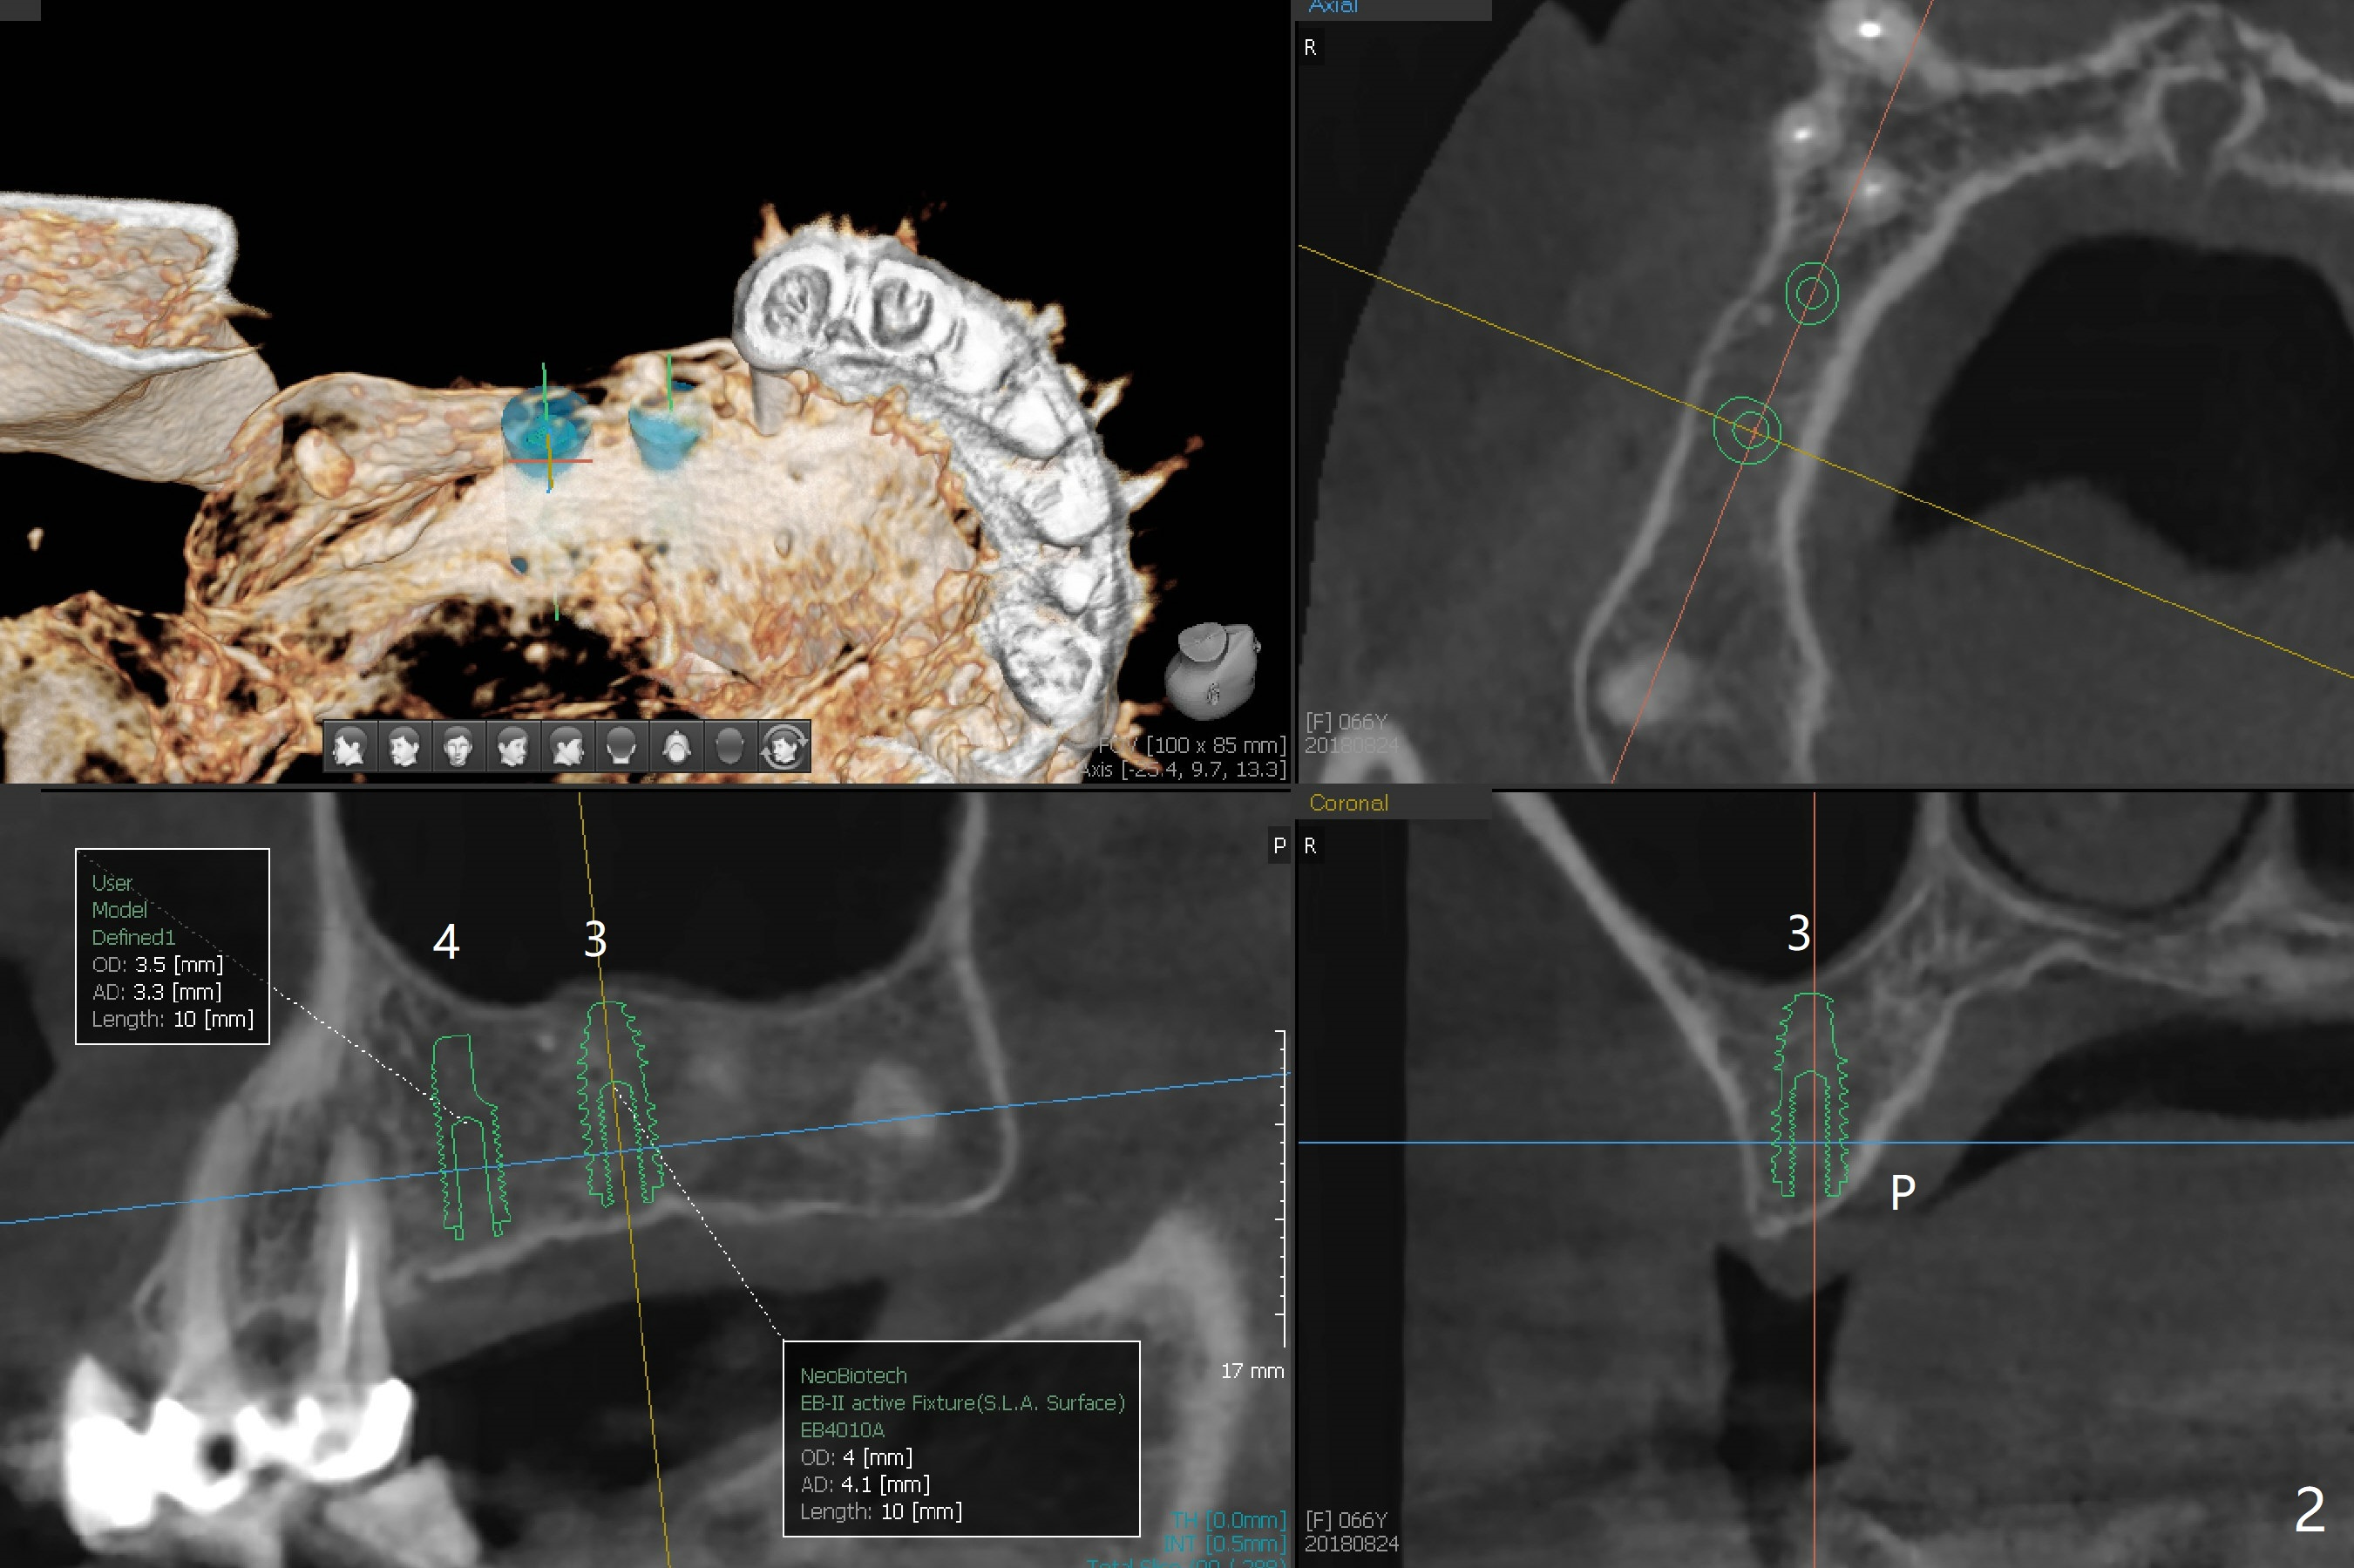

A 66-year-old woman requests implants at #3 and 4 (Fig.1). The main issue is loose bone with ~300 HU (Fig.2,3). Underprep must be a solution.